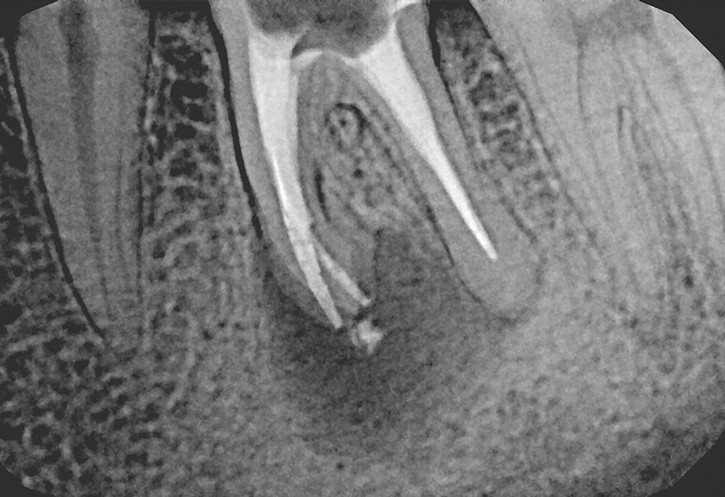

Przewlekły i bezobjawowy proces zapalny miazgi może być przyczyną chorób tkanek okołowierzchołkowych zęba. Choroby tych tkanek mogą mieć charakter niewielkich ziarniniaków, ale również rozległych torbieli zapalnych.

CHOROBY TKANEK OKOŁOWIERZCHOŁKOWYCH ZĘBA MOGĄ MIEĆ CHARAKTER NIEWIELKICH ZIARNINIAKÓW, ALE RÓWNIEŻ ROZLEGŁYCH TORBIELI ZAPALNYCH

W przypadku zaawansowanych postaci zapaleń miazgi oraz zapalenia tkanek okołowierzchołkowych obraz radiologiczny jest warunkiem rozpoznania. W takiej sytuacji standardem diagnostycznym są zdjęcia przylegające zęba, często wykonywane przy użyciu radiowizjografii na fotelu stomatologicznym w trakcie leczenia zęba. Przydatne jest również badanie RTG OPG pantomograficzne, które pokazuje w dwuwymiarowym obrazie zarówno uzębienie, jak i cały układ kostny szczęki oraz żuchwy.

Stożkowa tomografia komputerowa CBCT, ze względu na dokładne, trójwymiarowe obrazowanie 3D, bez zniekształceń ukazuje szczegóły anatomii zęba oraz okolicznych tkanek, wyjaśniając nierzadko problemy niemożliwe do zdiagnozowania standardowymi metodami.

Zarówno ziarniniak okołowierzchołkowy, jak i torbiel zębopochodna uszkadzają struktury okolicznej tkanki kostnej. Podobny proces jeszcze do niedawna był książkowym wskazaniem do interwencji chirurgicznej (resekcja wierzchołka korzenia, hemisekcja korzenia zęba wielokorzeniowego) lub nawet usunięcia zęba.